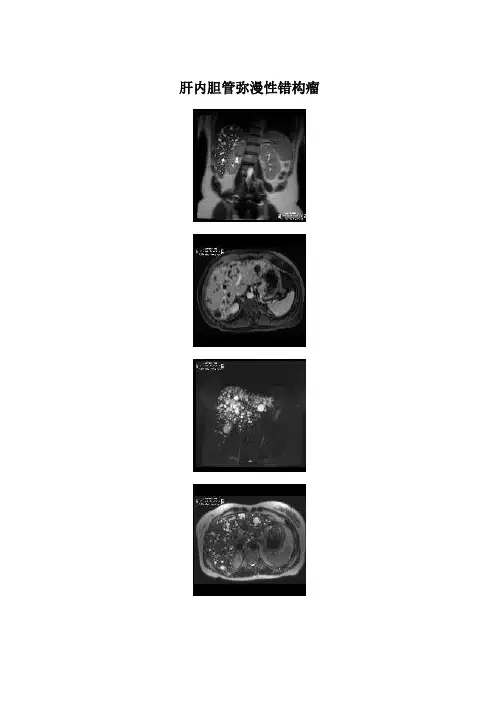

肝脏胆管错构瘤的影像表现及鉴别诊断宋段;薛明团;王玉林【摘要】目的:探讨肝脏胆管错构瘤的MRI表现特点,提高对该病的认识及诊断.方法:选取两院确诊的13例成人肝脏胆管错构瘤作为研究对象,通过分析其MRI表现,对该病系统性分析.结果:3例行穿刺检查确诊.所有患者均呈弥漫多发病变,12例病灶弥漫分布肝脏左右两叶,l例弥漫分布于肝脏右叶;病变信号均匀,大小不等,多数病灶小于10 mm,呈长T1长T2囊性信号,DWI呈低信号,增强无强化.磁共振胰胆管造影(MRCP)显示病灶沿胆管树走行并与胆管树不相通.结论:肝脏胆管错构瘤在MRI扫描上有特异性表现,通过认识这些征象,提高对该病的诊断及鉴别诊断.【期刊名称】《中国临床医学影像杂志》【年(卷),期】2016(027)009【总页数】4页(P640-643)【关键词】肝肿瘤;错构瘤;磁共振成像;诊断,鉴别【作者】宋段;薛明团;王玉林【作者单位】内蒙古赤峰学院附属医院MRI室,内蒙古赤峰024000;内蒙古赤峰学院附属医院MRI室,内蒙古赤峰024000;中国人民解放军总医院放射科,北京100039【正文语种】中文【中图分类】R735.7;R445.2肝脏胆管错构瘤是肝脏内少见的良性肿瘤样病变,是由于胚胎时期肝内小叶间胆管的发育畸形,从而导致形成大小不一的囊状结构[1],于1918年由Von Meyeburg首先描述发现,故又称为Von Meyebury Complex(VMC)。

结果:肝内胆管错构瘤在T1WI上信号低于肝实质,增强扫描无强化;T2WI病灶显示清楚,呈明显的高信号;FIESTA病灶呈高信号;MRCP显示多发小圆形高信号与胆管不相通。